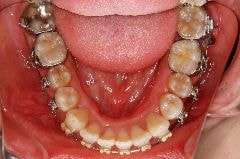

歯科矯正用アンカースクリューの使用例

例1)